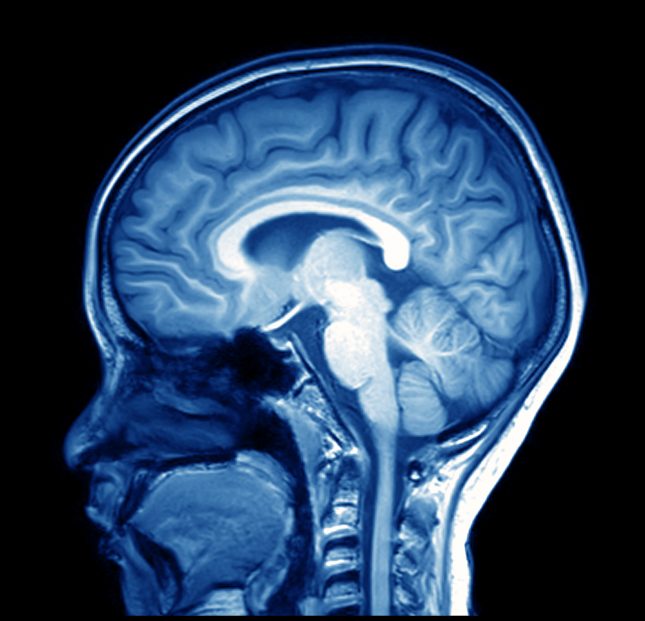

במחקר חדש שפורסם בכתב העת Scientific Reports, צוות של שבעה מדענים ממדינת ג'ורג'יה בנה תוכנת מחשב מתוחכמת שהצליחה לסרוק כמויות אדירות של נתוני הדמיה מוחית ולגלות דפוסים חדשים הקשורים למחלות מוחיות. נתוני ההדמיה המוחית הגיעו מסריקות הדמיית MRI פונקציונלית (fMRI), הדמיה המודדת את פעילות המוח על ידי זיהוי שינויים זעירים בזרימת הדם.

מודלי הבינה המלאכותית הוכשרו כדי ללמוד להבין הדמיית fMRI בסיסית ותפקוד המוח, ותורגלו על ידי מערך נתונים הכולל יותר מ-10,000 הדמיות שונות. לאחר מכן השתמשו החוקרים במאגרי נתונים רבים הכוללים יותר מ-1,200 אנשים, כולל אנשים עם הפרעה על ספקטרום האוטיזם, סכיזופרניה ומחלת אלצהיימר.